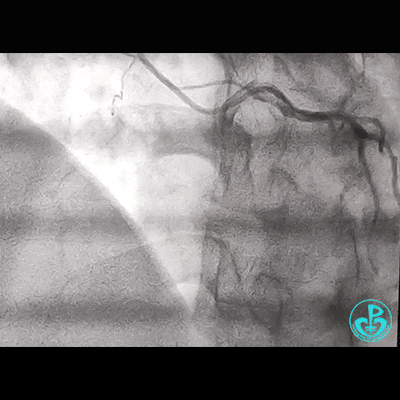

调整GC,重进导丝,先用1.5mm球囊,2.0mm球囊,3.5mm球囊……完成后扩!

此时,鞘管外GC已经扭曲,更换JR 4.0,看右冠开口。

反复操作GC,疑似右冠开口已经夹层,此时心电图无异常!

补3.5×12mm支架一枚。

这台20分钟就能完成的手术,耗时达2个小时!

锁骨下动脉迂曲,术中GC飞出,是造成故事的原因!